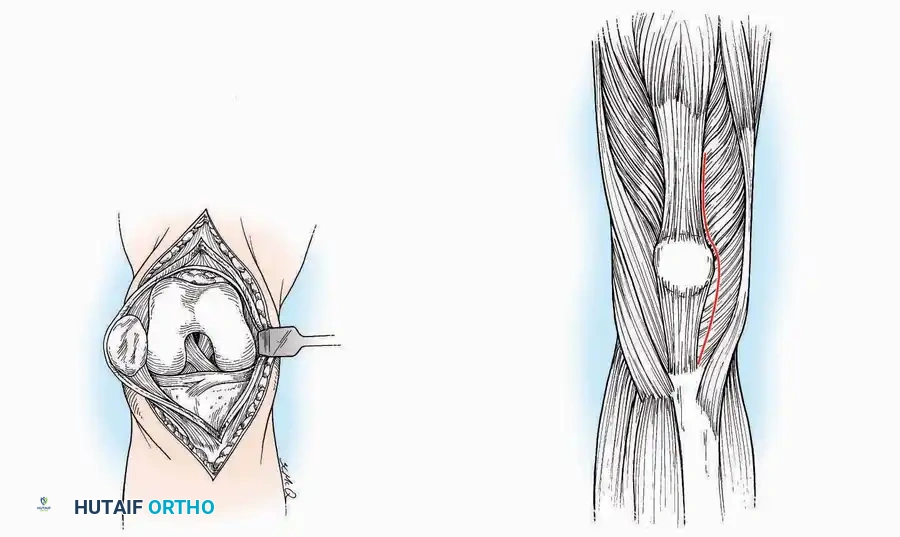

Anterior Approach

Indications: Total ankle arthroplasty (TAA), anterior ankle arthrodesis, and excision of anterior tibial/talar osteophytes (anterior impingement).

Surgical Technique:

* Incision: Make a 10 to 15 cm longitudinal incision over the anterior aspect of the ankle, centered exactly midway between the medial and lateral malleoli.

* Superficial Dissection: Incise the superficial fascia. Identify and protect the superficial peroneal nerve branches laterally and the saphenous nerve medially.

* Internervous Plane: The deep dissection exploits the plane between the Extensor Hallucis Longus (EHL) tendon (innervated by the deep peroneal nerve) and the Extensor Digitorum Longus (EDL) tendons (also innervated by the deep peroneal nerve).

* Neurovascular Bundle: Incise the extensor retinaculum. Carefully identify the anterior tibial artery and the deep peroneal nerve, which typically lie between the EHL and EDL, or directly deep to the EHL. Retract the neurovascular bundle laterally with the EDL, or medially with the EHL, depending on the specific anatomical variant encountered (lateral retraction is most common).

* Capsulotomy: Incise the anterior joint capsule longitudinally. Elevate the capsule subperiosteally from the anterior tibia and the talar neck to expose the entire tibiotalar articulation.